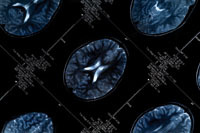

Scientists from the University of Oxford have broken the blood-brain barrier, allowing cancer drugs to be delivered to life-threatening cancers which have spread to the vital organ.

The study – in mice and tissue cultures – used a protein called TNF, which is able to seek out sites in the brain where the cancer has spread by recognising a marker found only on tumour blood vessels. TNF homes in on these sites and temporarily opens the blood-brain barrier (BBB) allowing drugs to pass from the blood system into the tumour.

The BBB is a protective shield that prevents potentially dangerous particles entering the brain, but also stops cancer drug reaching their target.

Researchers showed the TNF only broke down the BBB in blood vessels that pass through the tumour, leaving healthy parts of the brain undamaged by potentially toxic drugs.